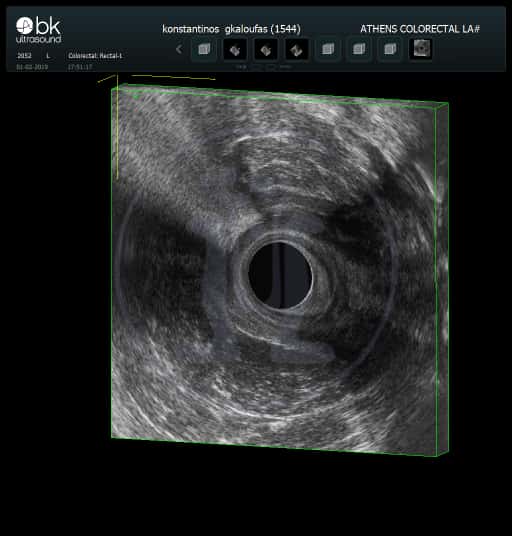

Ασθενής 44 ετών που εξετάσαμε δεύτερη φορά μετά από 14 μήνες έμεινε αθεράπευτος γιατί κανείς δεν ήθελε να τον αναλάβει. Είχε δύο ράμματα seton σε λάθος θέση ενώ στην σωστή θέση δεν υπήρχε ράμμα seton. Πολλαπλές επεμβάσεις είναι απαραίτητες για την τελική θεραπεία του προβλήματος του.